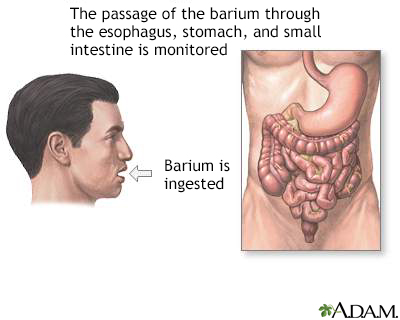

An upper GI and small bowel series is a set of x-rays taken to examine the esophagus, stomach, and small intestine.

Before the x-rays are taken, you must drink 16 to 20 ounces (480 to 600 milliliters) of a milkshake-like drink. The drink contains a substance called barium, which shows up well on x-rays.

An x-ray method called fluoroscopy tracks how the barium moves through your esophagus, stomach, and small intestine. Pictures are taken while you sit or stand in different positions.